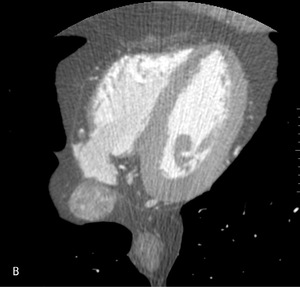

Rycina 1. Badanie tętnic wieńcowych metodą tomografii komputerowej. A. Rekonstrukcja MIP Inwers (maximum intensity projection) – widoczne liczne zwapnienia w lewej tętnicy wieńcowej oraz krytyczne zwężenie w jej środkowym segmencie. B. Rekonstrukcja VR (volume rendering) – krytyczne zwężenie środkowego segmentu lewej tętnicy wieńcowej oraz gałęzi diagonalnej. C. Warstwa poprzeczna (axial) – widoczna blaszka niskiej gęstości wypełniająca światło segmentu środkowego lewej tętnicy wieńcowej.

Ponieważ nie udało się uzyskać podczas badania obciążeniowego maksymalnej częstości rytmu serca (badanie wykonano podczas stosowania metoprololu w dawce 50 mg/24 h), a pacjenta należało uznać za obciążonego wysokim ryzykiem (płeć, wiek, obciążenie rodzinne, nadciśnienie tętnicze, hiperlipidemia, nikotynizm), zdecydowano o wykonaniu badania obrazowego – tomografii komputerowej tętnic wieńcowych. Wykonano:

- tomografię komputerową serca, w której odnotowano następujące wyniki:

– Wskaźnik uwapnienia – 797.

– Tętnice wieńcowe: pień lewej tętnicy wieńcowej (LTW) bez zmian.

– Gałąź przednia zstępująca (GPZ): segment 6 z blaszką niskiej gęstości ~30% (remodeling dodatni ściany!); segment 7 – długa blaszka (12-15 mm) niskiej gęstości z remodelingiem dodatnim ściany, zwężająca w części środkowej krytycznie światło ~95%. Referencja proksymalna 4,3 mm, dystalna 2,1 mm; segment 7 za zmianą i segment 8 z wielopoziomowymi blaszkami niskiej gęstości ~30% (ryc. 1).

– Gałąź okalająca (GO): segment 11 – koncentryczne blaszki niskiej gęstości ~20-40% z remodelingiem dodatnim ściany naczynia (!). Gałąź marginalna 1 – proksymalnie blaszki niskiej gęstości ~40%. Obwód niewidoczny. Gałąź marginalna 2 – proksymalnie koncentryczne blaszki niskiej gęstości ~40%.

– Prawa tętnica wieńcowa (PTW): segment 1 – uwapnione wielopoziomowe zmiany ~30% przechodzą w blaszkę niskiej gęstości ~60%; segment 2 – wielopoziomowe blaszki mieszanej gęstości ~30%; segment 3 – blaszki niskiej gęstości ~30-50% z remodelingiem dodatnim ściany naczynia (!). Obwód – zmiany przyścienne (ryc. 2).

– Wynik oceny czynności mięśnia lewej komory: ESV (end systolic volume) – 48 ml, EDV (end diastolic volume) – 173 ml, SV (stroke volume) – 124 ml, EF (ejection fraction) – 71%, CO (cardiac output) – 6187 ml/min, czynność serca podczas badania – 49/min.